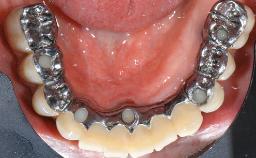

This case describes the ongoing management of a 64-year-old healthy, non-smoking female patient with erosive oral lichen planus (OLP) affecting the gingivae and the buccal and lingual mucosa. The peri-implant mucosa was also affected subsequent to implant placement. The patient had osseointegrated implants (four in the maxilla, four in the mandible) placed following extraction of hopeless teeth and a healing period. The patient had a history of OLP prior to implant placement and had been referred to an oral-medicine specialist for definitive diagnosis and treatment. She exhibited generalized oral mucosal involvement. Following a clinical assessment, biopsy, and blood tests, she was treated with topical corticosteroids. Systemic prednisolone was reserved for severe flare-ups. Amphotericin lozenges were used in combination with corticosteroid treatment to prevent the development of oral candidiasis.

# of Implants | 8 |

Retention | Screw-retained, with 4 or more splinted implants Screw-retained, with 4 or more splinted implants |